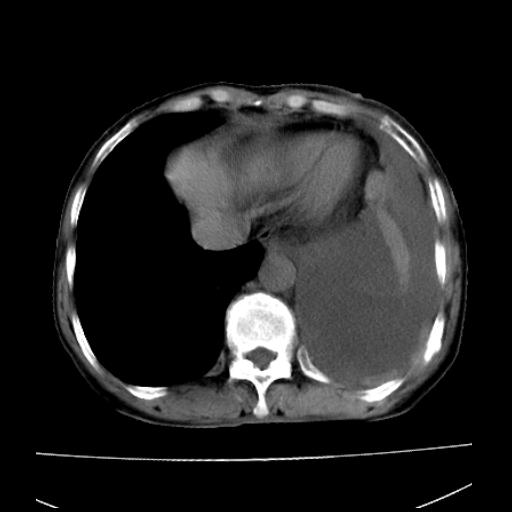

以下是引用随光逐影在2010-3-24 19:15:00的发言:[br]结合病史,考虑双肺及纵隔淋巴结多发转移、左侧胸膜转移并左侧大量胸水,左下肺膨胀不全。

以下是引用zxl51642在2010-3-24 18:49:00的发言:[br]结合乳腺癌术后病史,考虑双肺及纵隔淋巴结多发转移、左侧胸膜转移并左侧大量胸水、左下肺膨胀不全。